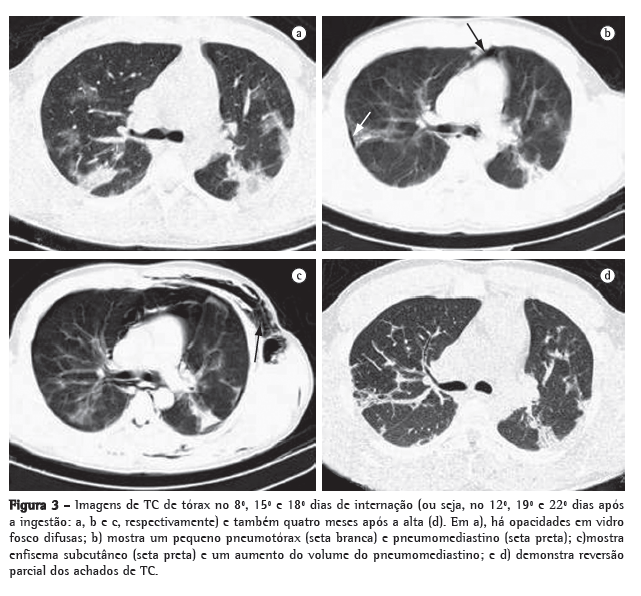

No segundo dia de internação (6º dia após a ingestão), o paciente apresentou hemoptise. A radiografia de tórax realizada no 8º dia após a ingestão mostrou infiltrado alveolar localizado (Figura 2b). Opacidades pulmonares, pneumomediastino, pneumotórax e enfisema subcutâneo foram detectados na TC de tórax (Figura 3). No sétimo dia de internação, os parâmetros gasométricos pioraram (Figura 1), e o paciente foi submetido a um segundo ciclo da mesma terapia imunossupressora. Posterior­mente, apesar de um episódio de neutropenia febril, ele se recuperou gradualmente e recebeu alta hospitalar, em bom estado, após quatro semanas, sem necessidade de oxigenoterapia domiciliar. Após quatro meses, o paciente estava trabalhando novamente e não tinha queixas, a não ser por dispneia após esforço físico intenso. Na ausculta torácica, ainda se podiam ouvir crepitações nos campos pulmonares inferiores, e havia sibilância universalmente distribuída, juntamente com atrito pleural no hemitórax direito. A TC de tórax realizada quarto meses após a alta também é mostrada na Figura 3.

Consequentemente, há inflamação, com recrutamento de leucócitos e fibrose pulmonar tardia, levando a hipoxemia que não responde ao tratamento. Essa fisiopatologia geralmente é confirmada por achados radiológicos,(4) como as opacidades em vidro fosco difusas demonstradas no presente relato de caso.(4) Além disso, observamos pneumomediastino, pneumotórax e enfisema subcutâneo, que são complicações comumente atribuídas à toxicidade pulmonar do paraquat.(5)